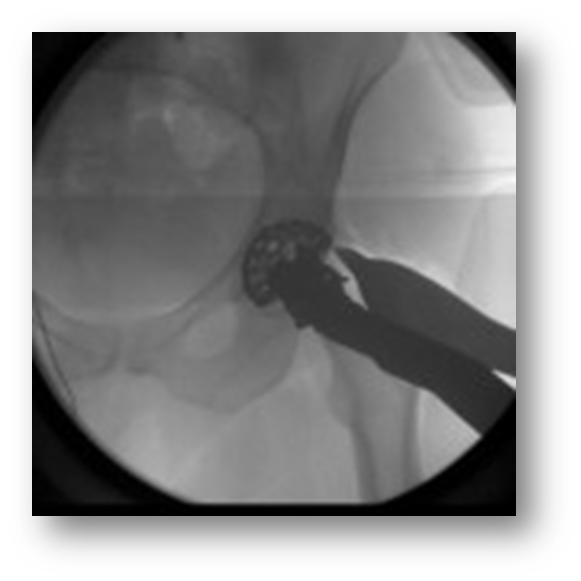

Acetabular reaming

Acetabular implantation

Final Fit